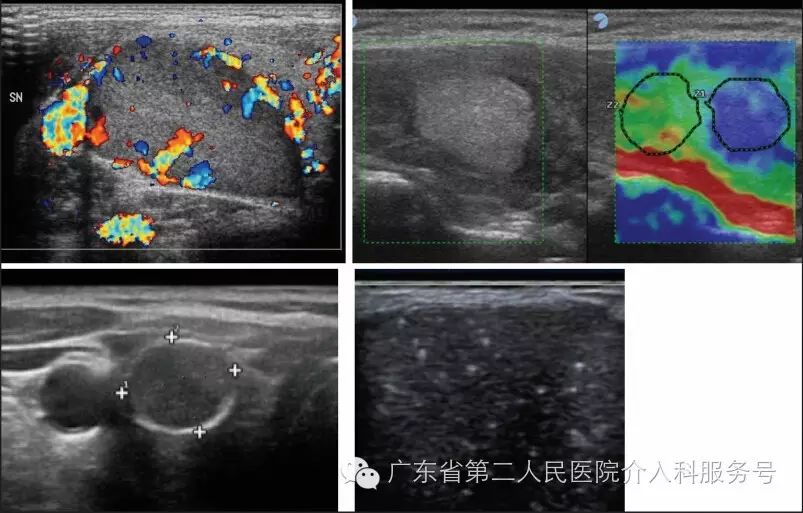

上图为:中度风险结节超声特征(左→右):1.有中央血管的等回声结节;2.弹性显像显示硬度高的等回声结节;3.有粗大钙化的等回声结节;4.有不明高回声斑点的等回声结节。